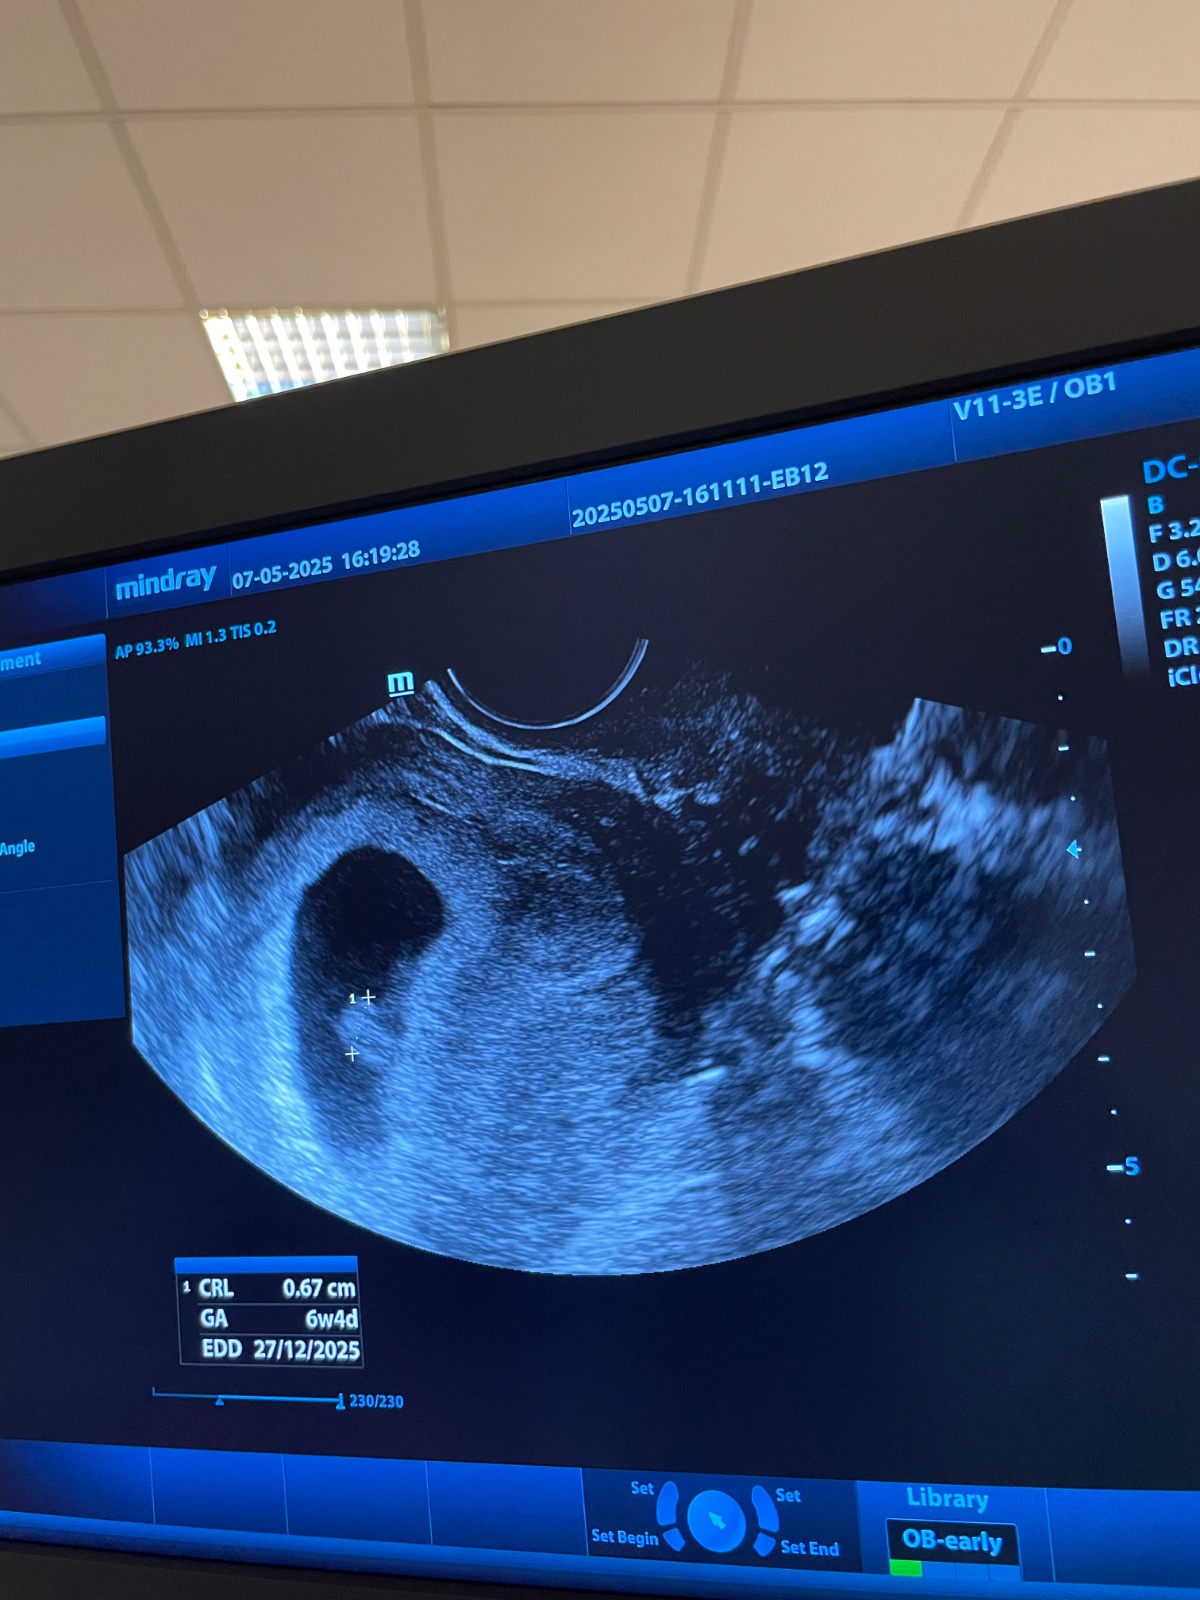

@anonym_autor ja som mala 5+5 zltkovy vak a gedtacny a o tyzden 6+5 uz bol aj olod a bijice srdiecko 🙂

@anonym_autor 4+6 som bola na gynde a bolo vidno len zltkovy vak, o dva týždne 6+6 bolo vidno gestacny vak, zltkovy, plod so srdiečkom.. sono bolo skoro preto nebolo vidno plod takze nádej tam je ☺️ tie dva týždne pre mna boli stresujúce či všetko bude tak ako má byť